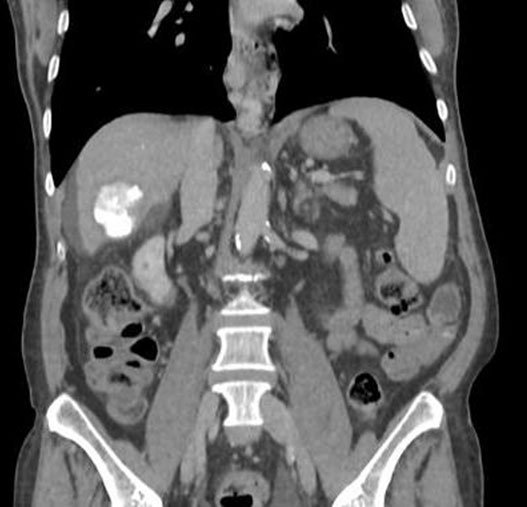

What is it?

Radioembolization is a minimally invasive procedure that combines embolization and radiation therapy to treat liver cancer. Tiny glass or resin beads filled with the radioactive isotope yttrium Y-90 are placed inside the blood vessels that feed a tumor. This blocks the supply of blood to the cancer cells and delivers a high dose of radiation to the tumor while sparing normal tissue. It can help extend the lives of patients with inoperable tumors and improve their quality of life.

Why (Indications)?

Primary infiltrative / multifocal HCC

It is a palliative treatment, which means it does not provide a cure but instead helps slow down the growth of the disease and alleviate symptoms.